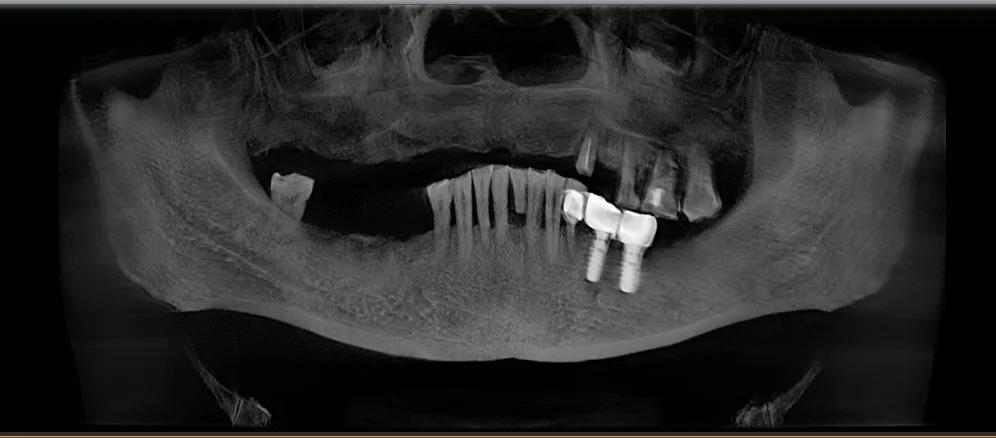

那时候因为年龄偏大,加上技术发展没有到,不能在上颌种植满口牙,只能在左下颌种了两颗新牙,正好对着左上颌残存的四颗老牙。

△第一次种植